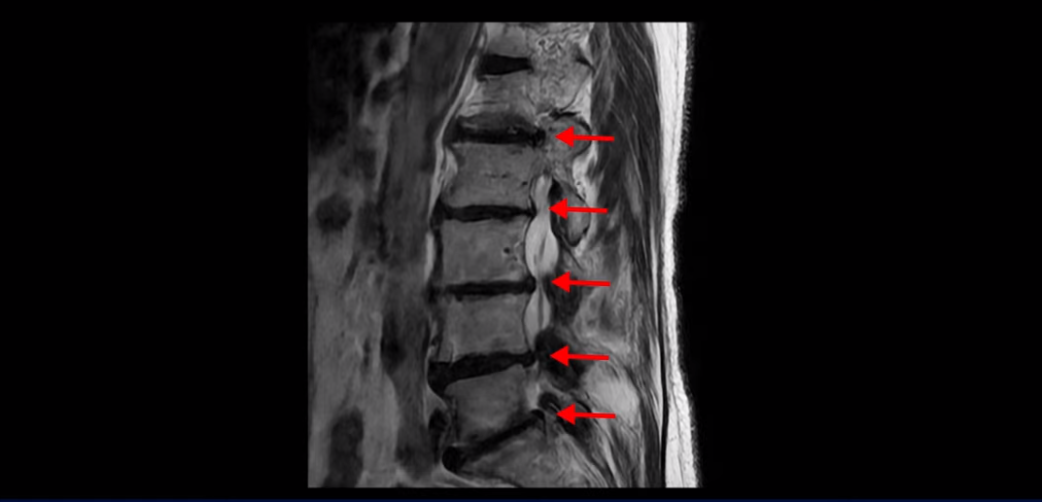

이분 MRI를 보고 설명해 드린 후 어떻게 허리 여러 마디에서 신경이 심하게 눌려 보이는 협착증 환자가 수술 없이 좋아질 수 있는지, 또 치료는 어떻게 하는지 설명해 드리겠습니다.

이분 MRI 보시다시피 허리 다섯 마디가 전부 다 퇴행이 심합니다.

특히 4번 5번에는 심한 중심성 협착이 있고,

5번 1번에는 황색인대가 골화되어 왼쪽 신경 나가는 길이 좁아져 있습니다.

그래서 왼쪽 엉덩이와 다리 통증이 더 심합니다. 이렇게 신경 구멍들이 좁아져 있고 신경이 눌리니까 엉덩이와 다리가 너무 저리고 아프고 힘도 빠져서 몇 걸음도 걷기 어려우니까 지팡이를 짚고 저녁에도 아파서 잠을 못 자는 겁니다.